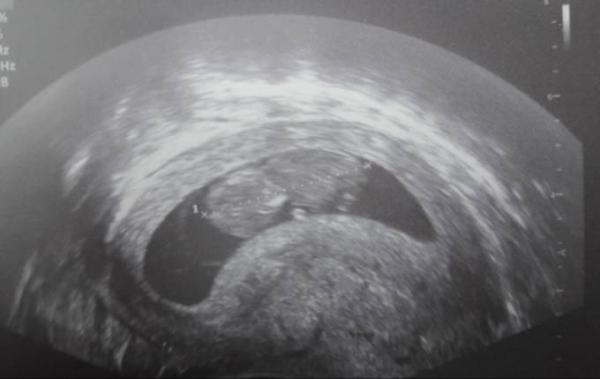

Hallo ihr, ich habe schon seit Mitte August fleißig mitgelesen und jetzt wage ich den Schritt mit in den Aprilbus einzusteigen. Zu mir: Ich bin 28 Jahre alt und es ist bereits meine 10. Schwangerschaft, aber ich habe nur 1 gesunde Tochter von 4,5 Jahren. Aber schon 8 Fehlgeburten, wovon der eine Teil schon vor meiner Tochter war und der andere Teil vor der jetzigen Schwangerschaft. Ich bin natürlich mega ängstlich, weil bei mir die Wahrscheinlichkeit einer erneuten Fehlgeburt natürlich deutlich höher ist. Aber ich versuche positiv zu denken. Aufgrund meiner Risikoschwangerschaft habe ich natürlich direkt ein Beschäftigungsverbot erhalten. Heute hatte ich wie alle 14 Tage einen Termin bei meiner FÄ. Danach war ich erstmal total erleichtert. Dem kleinen Wurm geht es gut, ist 3,66 cm groß. Dies entspricht SSW 10+4, also ET wäre somit der 20.04.2020 Ich hoffe soo sehr, dass es gut geht. Anbei auch ein Bild

Bild zu Darf ich auch noch mitfahren? - Forum für April - Mamis